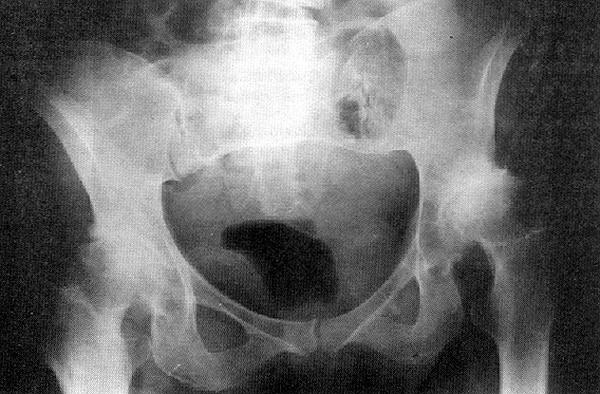

DIAGNÓSTICO Radiológico : – Pinzamiento de la interlínea articular – Esclerosis subcondral – Signo de Kiembock – Geodas – Osteofitos – Deformaciones en las superficies articulares

FASES DE LAS COXARTROSIS  Primera fase o incipiente Cambios en el aspecto del cartilago. Poco dolorosa, dsalvo en marchas prolongadas y permanencia de pie. Signos radiográficos y clinicos poco pronunciados.  Segunda fase o evolucionada. Destrucción del cartílago. Aparece rigidez y posiciones viciosas. El dolor aumenta y es persistente.  Tercera fase o final. Pérdida total del cartílago, osteofitos., signos óseos y capsulares más evidentes. Dolor muy intenso. Impotencia funcional muy marcada (posiciones viciosas persistentes)